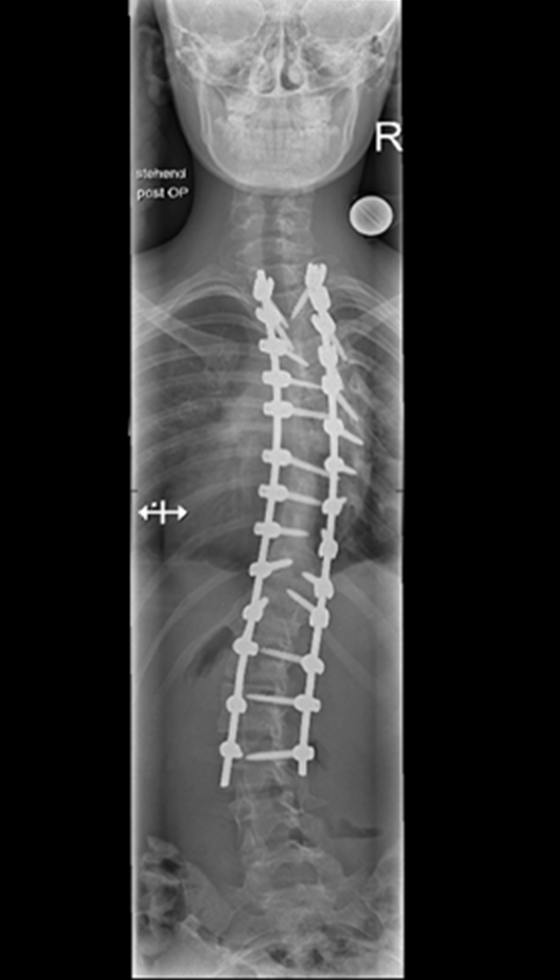

Gallery : Before - After